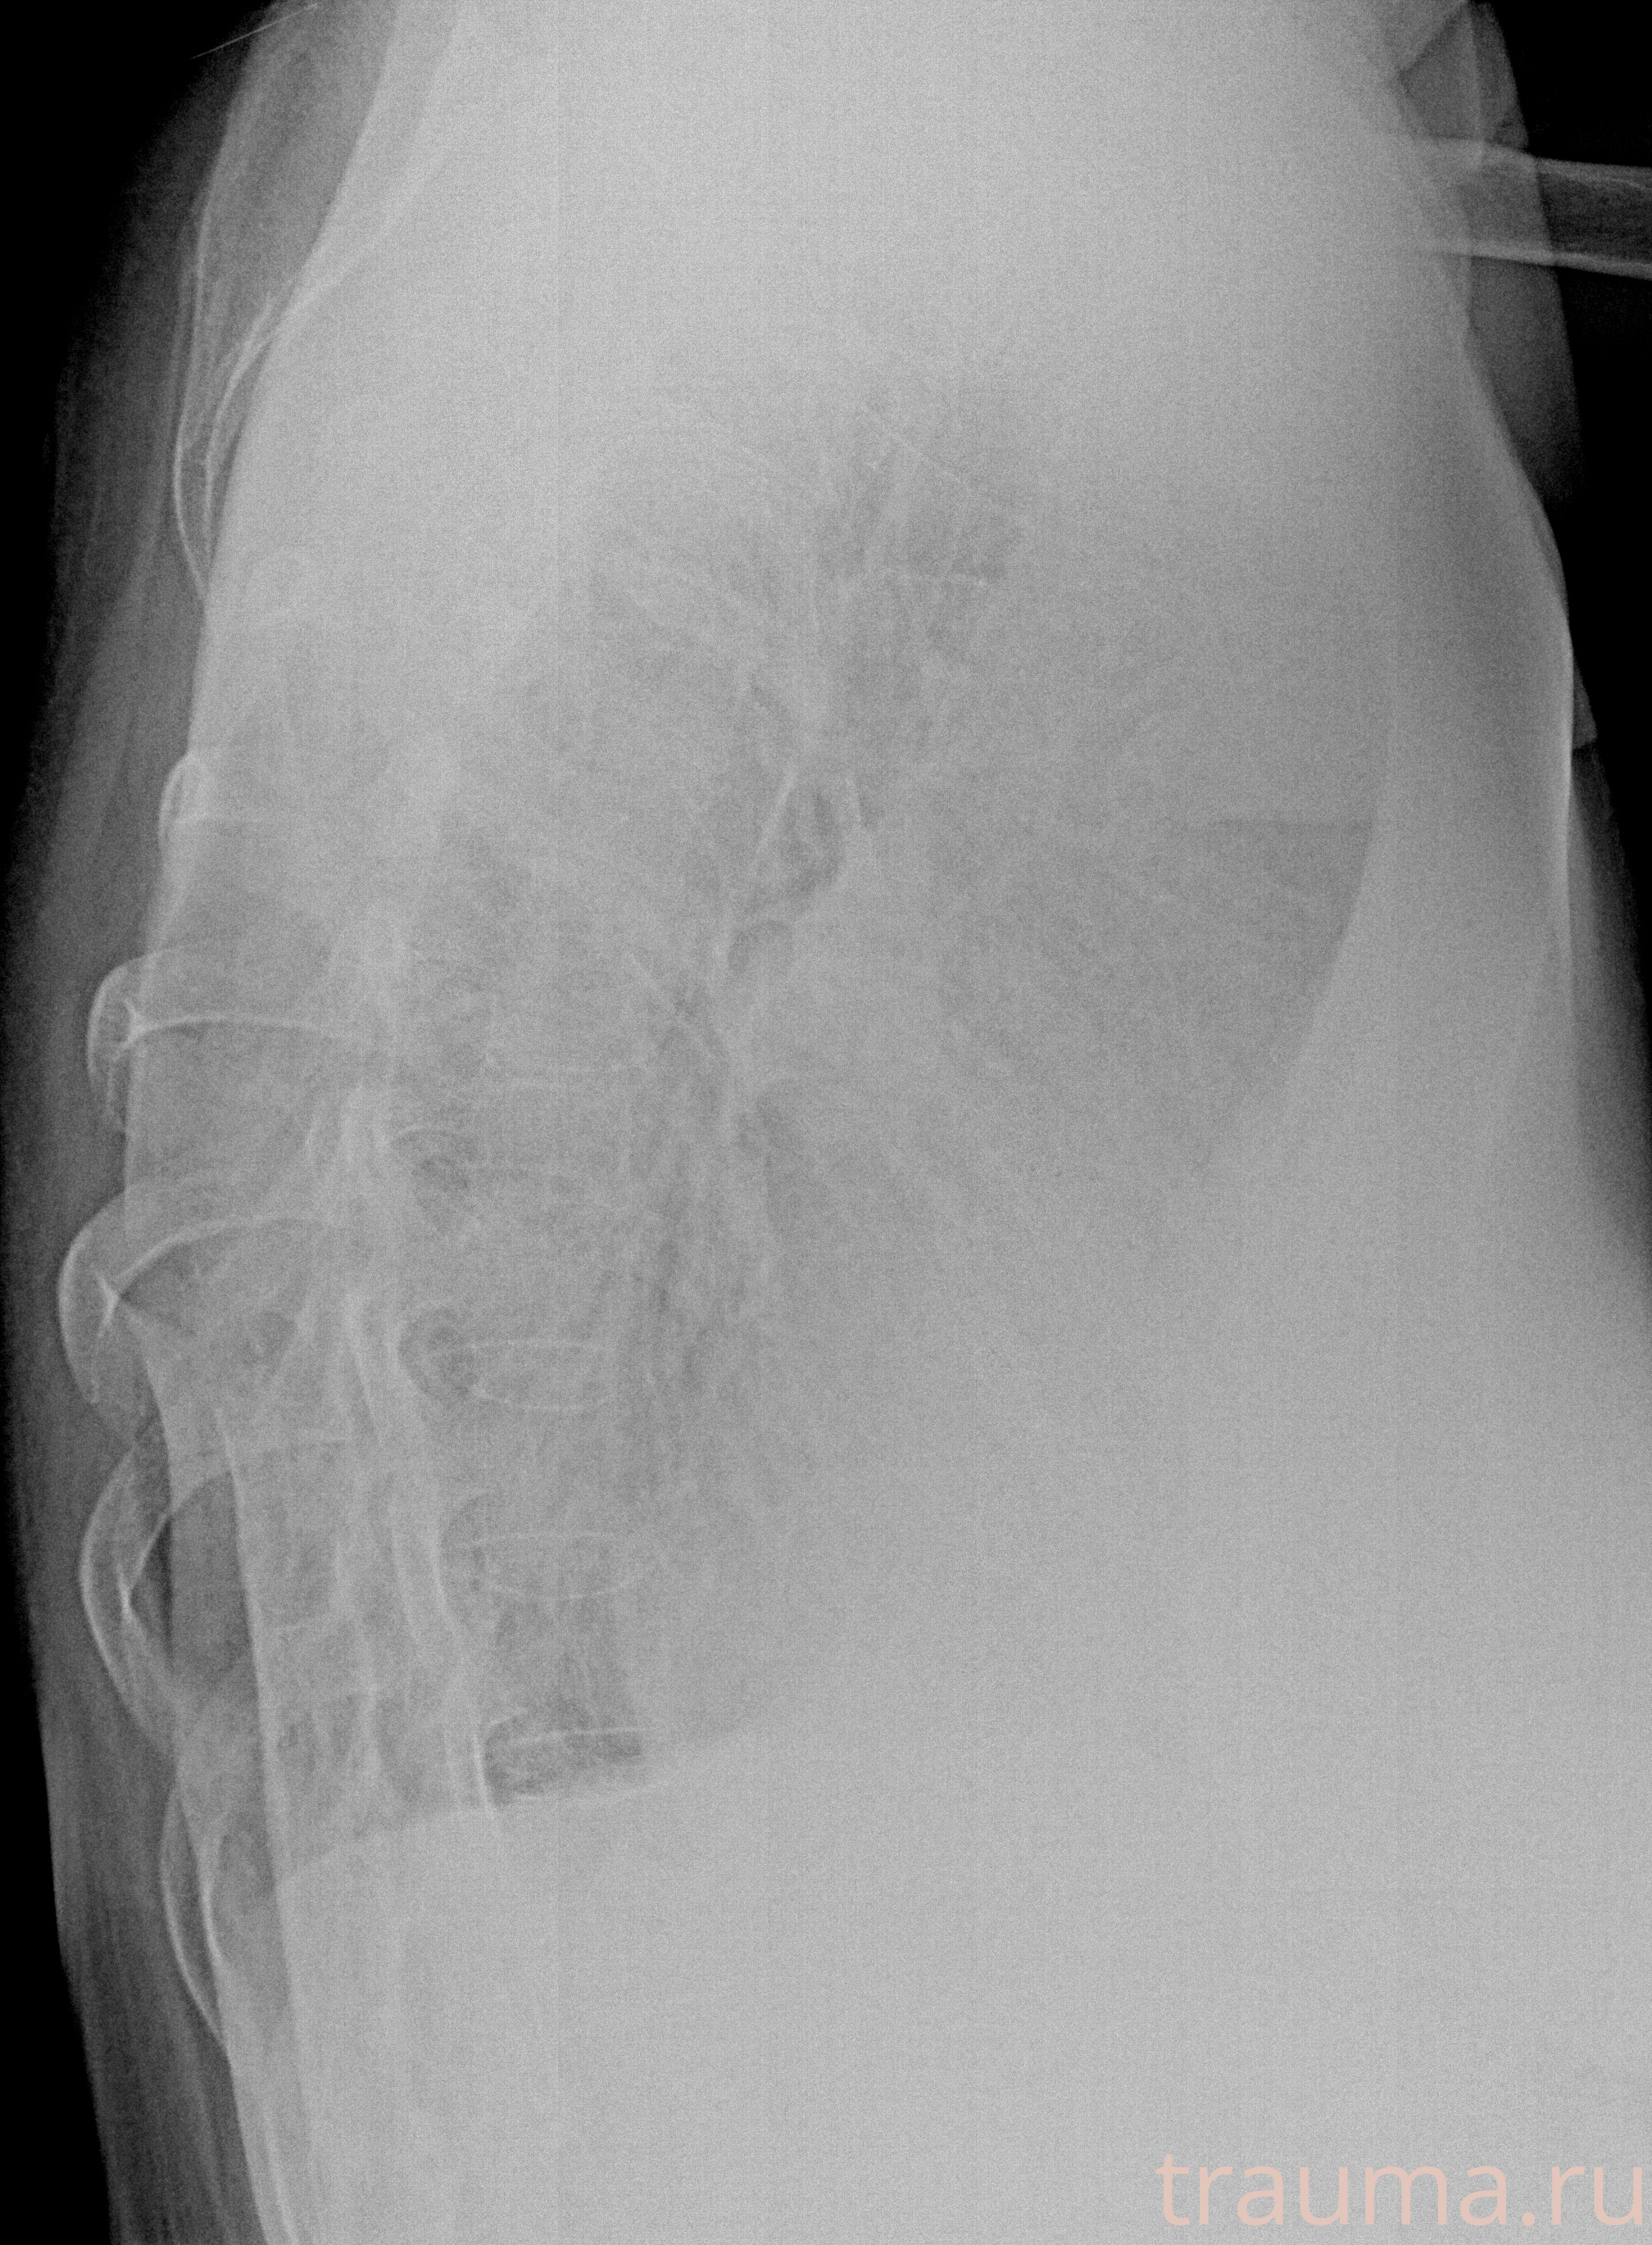

Рентген на дому: по вашему адресу приезжает врач-рентгенолог, травматолог-ортопед с мобильным рентгеновским аппаратом, проводит диагностику травмы или заболевания, делает необходимые рентгенограммы, дает рекомендации по дальнейшему лечению. Получить качественные снимки в домашних условиях возможно благодаря уникальной методике, разработанной МосРентген Центром для института  Склифосовского

при переломе шейки бедра и пневмонии от компании МосРентген Центр - партнера Института имени Склифосовского